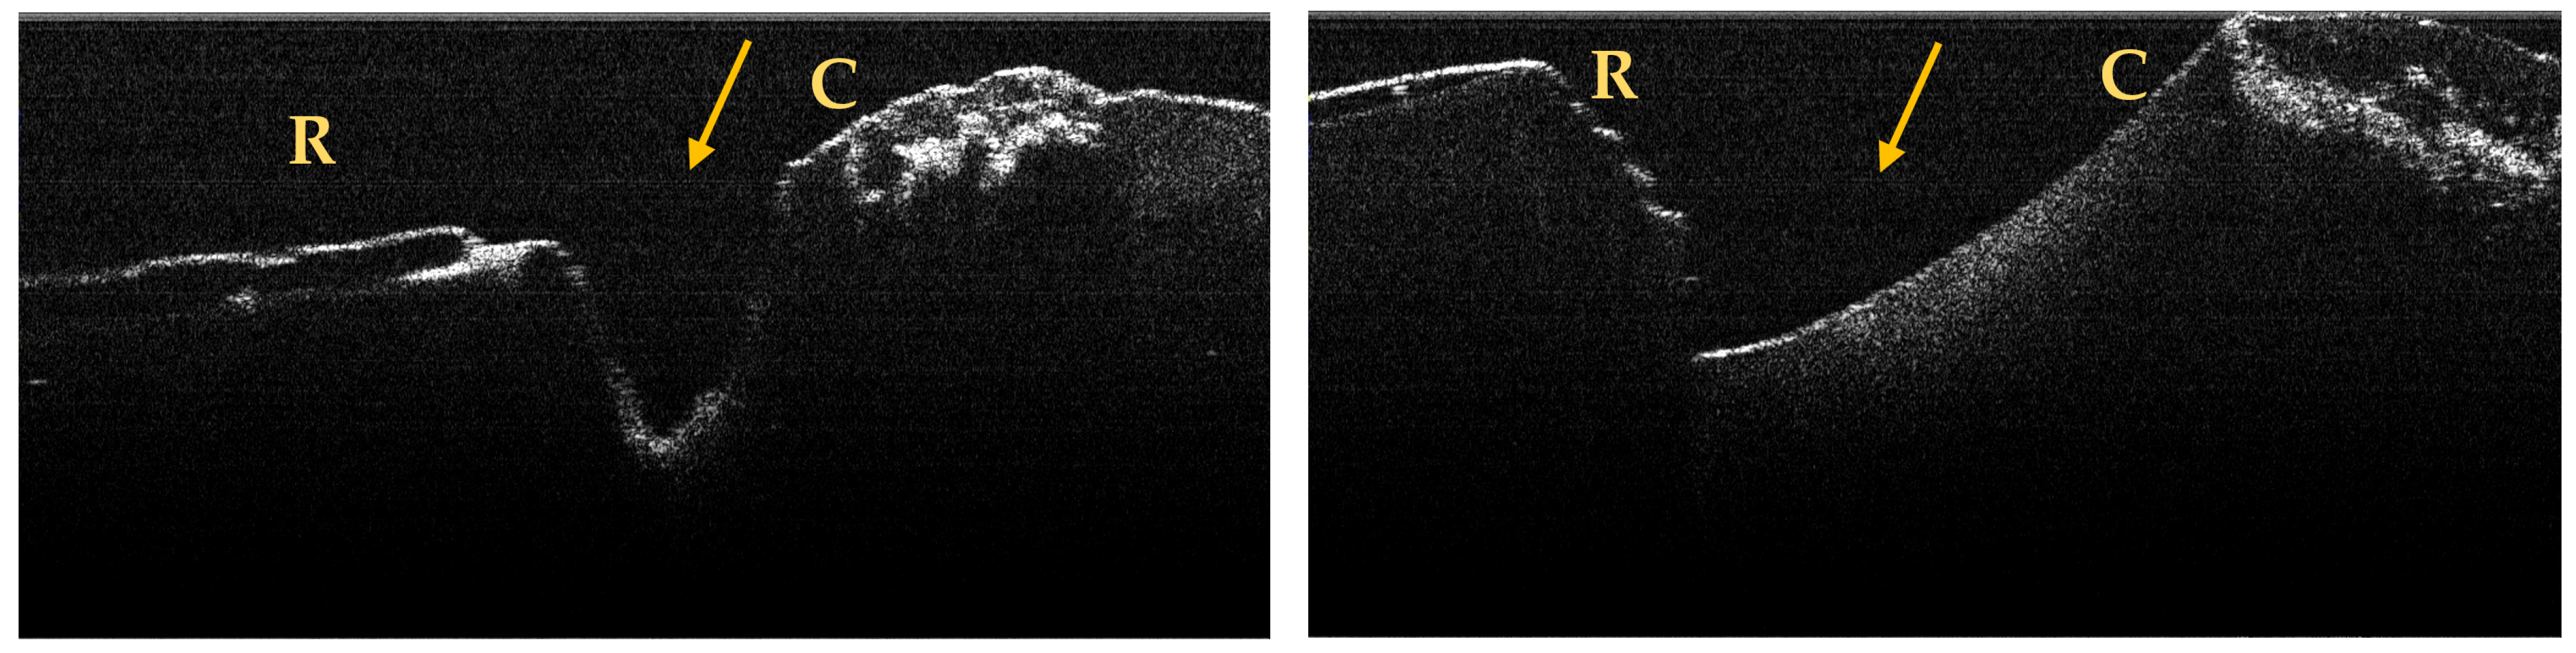

3.2. OCT Examination of Teeth Included in the Study